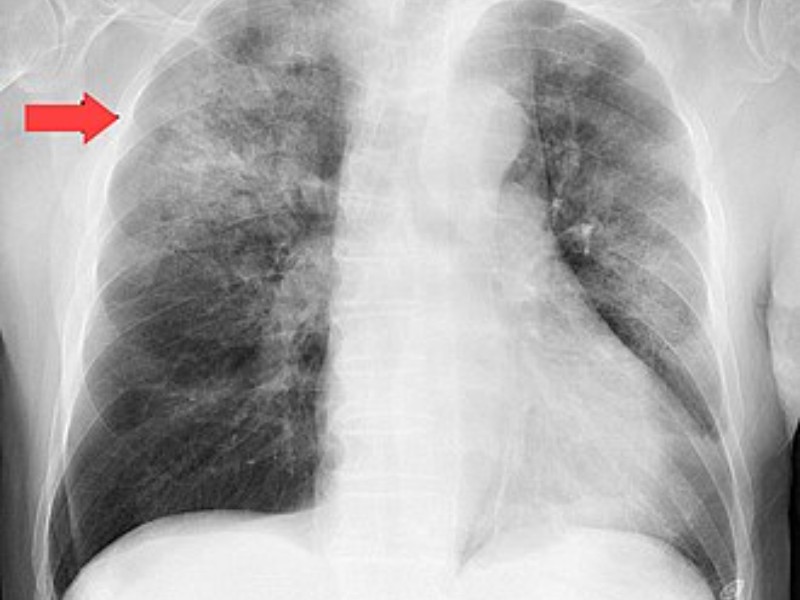

La neumonía es una infección respiratoria aguda que afecta a los pulmones. Puede ser causada por virus, bacterias u hongos, que provocan que los pulmones se llenen de líquido o pus, lo que dificulta la respiración y reduce el flujo de oxígeno en el cuerpo.

BACTERIA STREPTOCOCCUS PNEUMONIAE ES LA RESPONSABLE DE LA NEUMONÍA

FUENTE: SECRETARÍA DE SALUD